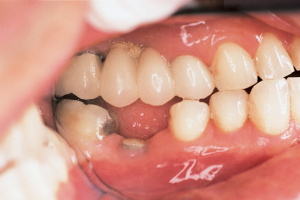

After the pilot hole was made, a depth gauge indicator was placed into the pilot osteotomy, and a periapical radiograph was obtained (Figure 3). This revealed the depth and mesial distal position of the initial pilot hole prior to the final enlargement. This step is an important conservative exploratory guide for the rest of the surgery.2 At this point, a self-centering soft tissue trephine was placed into the pilot hole, driven by a contra angle dental drill, and a circular, soft tissue donut of tissue was cut down to the bone and removed, creating a precise soft tissue channel to the alveolar bone (Figure 4). The

final enlargement was performed through this conservative channel, precisely matching the diameter and depth of the implant.

The BASIC implant used in this case is a self-tapping stage-one implant that is screwed into place with a simple ratchet. This particular implant system is unique because it utilizes a hex-recess hole that accommodates resin cementable customized posts and cores.3 Because this particular protocol is so quick, simple, and conservative, it is possible to obtain impression records of the implant site and the opposing arch at the time of surgery. Thirty minutes is more than adequate time required to perform this phase of the implant treatment ( Figure 5).